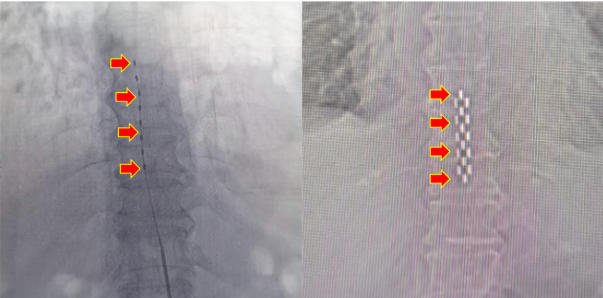

臨時刺激電極(左)  VS 永久刺激電極(右)

術前(左) VS 術后(右)

最初神經外科予以臨時脊髓電刺激治療,患者左足血供明顯好轉,創面加速愈合、結痂。在臨時治療效果顯著的情況下,予以二期手術,植入永久刺激器。術后患者疼痛明顯緩解,缺血情況顯著好轉,成功保肢。日前,患者恢復順利,患者及家屬對治療效果表示滿意。